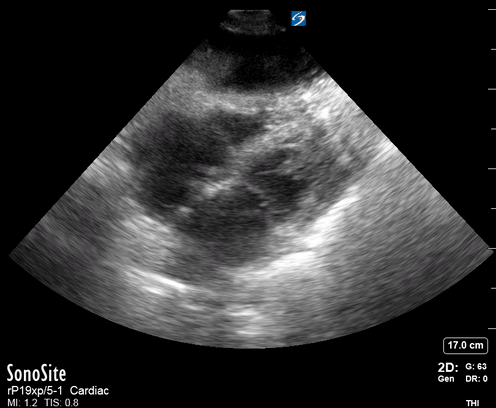

Equality: is the RV dilated or significantly impaired?

Normally, the RV is a low-pressure, thin-walled, high-compliance chamber that wraps anteriorly around the muscular, cone-shaped LV. The normal RV : LV diameter ratio is 0.6 : 1.

When the pulmonary artery pressure rises, the RV will dilate, altering the normal RV:LV ratio. Although sacrificing sensitivity, the use of equality (1:1 ratio) as a cutoff can achieve a specific estimation of RV strain. If imaged correctly by a trained operator, the presence of an RV:LV ratio > 1 is highly specific for RV strain.

RV dilation can be acute, chronic, or acute-on-chronic. However, in patients presenting with undifferentiated chest pain, shortness of breath, hypotension or syncope, the presence of any RV dilation should raise suspicion for acute pulmonary embolism (PE). Furthermore, in a patient in shock, the presence of RV strain may signal the need for aggressive therapy – emergency thrombolysis.

THE VIEWS

The A4C view provides an accurate chamber size comparison. However, achieving a proper A4C view (avoiding foreshortening or ballooning, and visualising the four chambers with a vertically oriented interventricular septum) can be a challenging exercise of image acquisition. Additionally, the PSAX view at the level of the papillary muscles shows both LV and RV side by side and is useful to assess function and size. When RV pressure is high, the septum will be pushed and flattened towards the LV, resulting in the characteristic “D-shaped” LV or “D sign”.